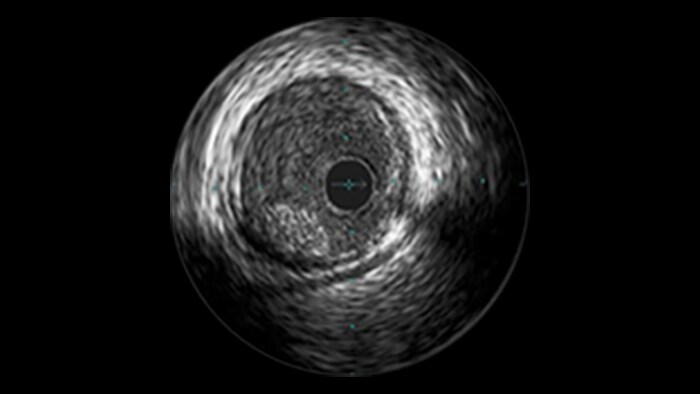

Diffuse Disease

Approximately 20% of the coronary lesions treated today are long and diffuse.1,2

Clinical challenges

– Stent length is an independent predictor of in-stent restenosis and thrombosis.

– Stenting long segments with multiple and or overlapping stents may lead to injury to the vessel wall integrity.

– Diffuse CAD may be underestimated by evaluation with coronary angiography.

– Determining reference vessel sizing can be challenging when the vessel is diffusely diseased.